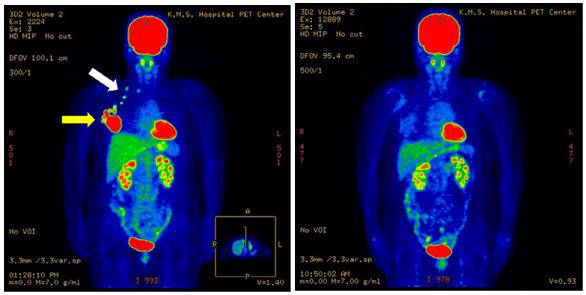

(圖2)57歲女性,右乳癌進(jìn)展期。左圖為治療前PET-CT圖像。腫瘤病灶(黃色箭頭),腋窩淋巴結(jié)轉(zhuǎn)移,鎖骨淋巴結(jié)轉(zhuǎn)移(白色箭頭)。右圖為治療后5年8個(gè)月的圖像,未復(fù)發(fā)。